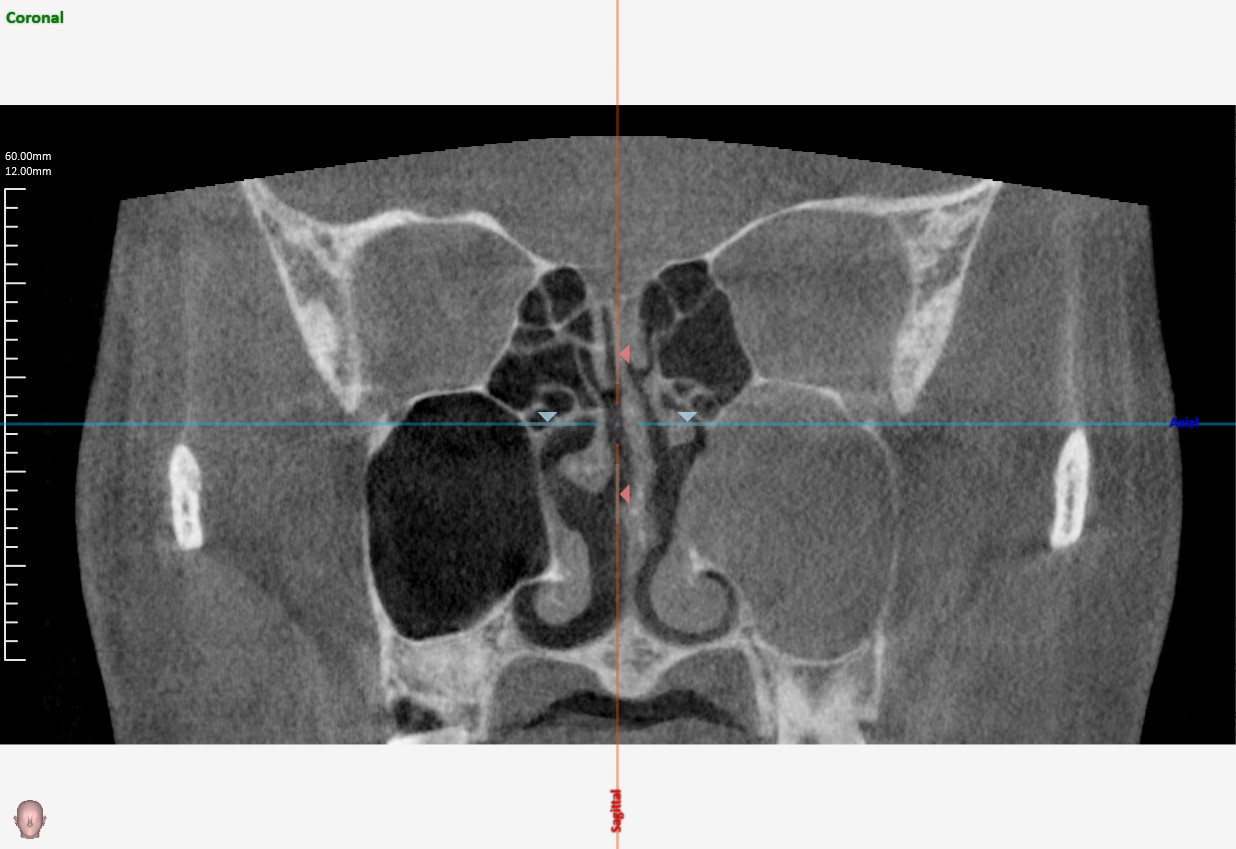

副鼻腔CT

• 特殊な副鼻腔炎(う歯による副鼻腔炎、真菌による副鼻腔炎)を疑う場合

• 副鼻腔の腫瘍を疑う場合

• レントゲンで病変がはっきりしない場合 など